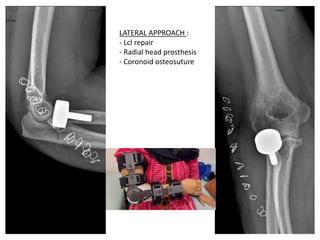

LATERAL APPROACH :

- Lcl repair

- Radial head prosthesis

- Coronoid osteosuture